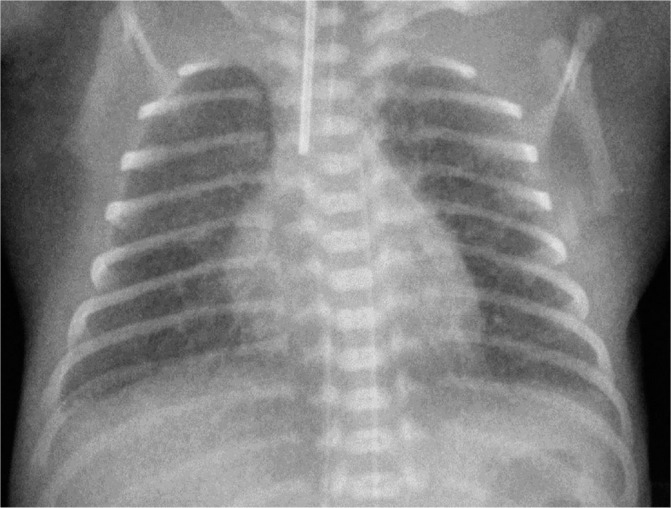

Case report: We present a case of an extremely preterm infant with persistent PTX who was successfully treated with fibrin glue. In addition, we present a two-and-a-half-year corrected age follow-up focusing on respiratory problems, motor development and sensory organs. Furthermore, we touch upon the related ethical issues.

Conclusions: Fibrin glue should be used to treat persistent PTX even in an extremely preterm infant. No adverse effects were observed. At the two-and-a-half-year corrected age follow-up, despite severe bronchopulmonary dysplasia development, no serious pulmonary problems were observed. However, the child's development is uncertain. This situation raises important ethical issues concerning saving the lives of infants at the limit of viability.